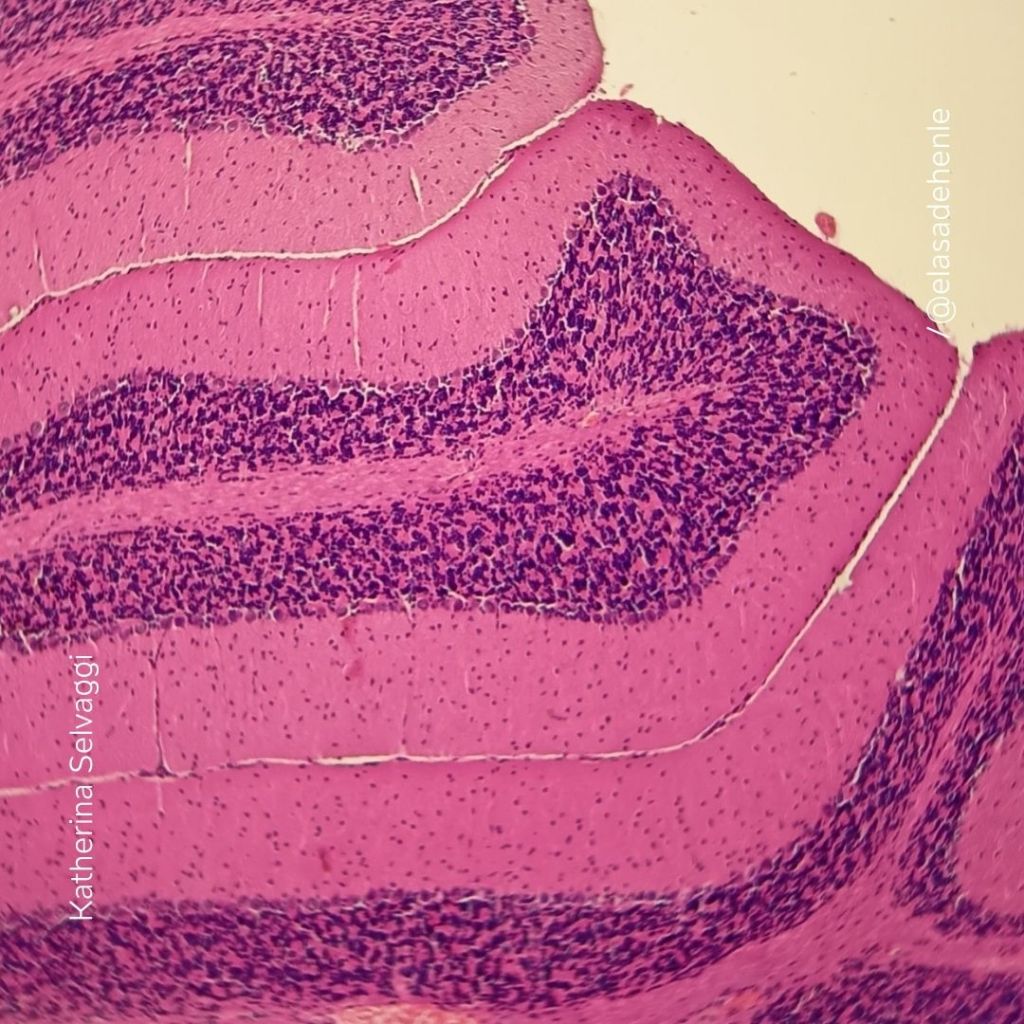

Hematoxilina y eosina

Cerebelo

Proyecto independiente